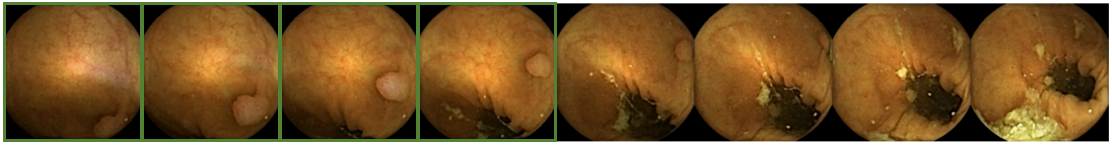

With regard to the specific goal of polyp detection, most of the published systems have been reported and validated as automatic detection methods. However, because of legal and practical reasons, these systems cannot be used for automatic diagnosis and can only be deployed as decision support systems which filter the whole set of frames to allocate physician’s attention to those images that show potential polyp structures. In most cases, this is a needle-in-haystack problem because of the occasional appearance of images with these pathologies. Figure 1 shows two sequences from different procedures where a polyp is observed. It is important to point out that, in both procedures, those are the only images of the whole procedure where a polyp is visible. Figure 2 shows some random images from the same procedures.

Figure 12 shows the second sequence of images in Figure 1 with the output of the system represented by adding a green square around the frames where the system has detected a polyp. Although in this example the system missed two frames where the polyp is present, the detection in four frames is sufficient for the physician to establish the diagnosis.